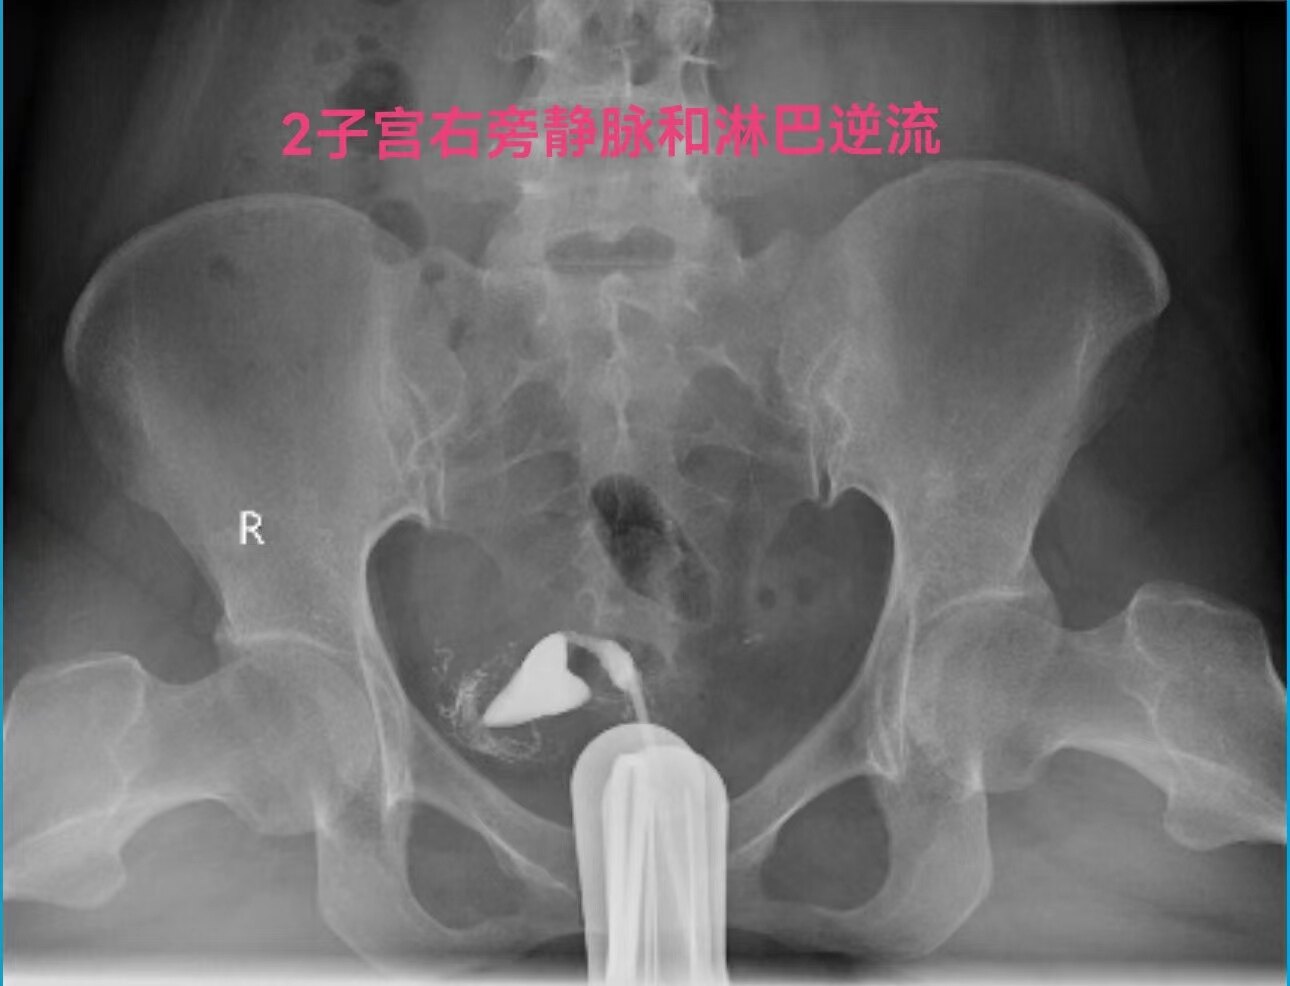

在做子宫输卵管造影检查时:当所用造影剂为碘油,出现静脉和淋巴管逆流时,立即停止造影检查是对的。因为碘油和血液不能相容混合一起,碘油会形成油栓。因此,当碘油进入静脉和淋巴管后会进入下腔静脉,进入右心房,进而进入肺动脉,形成肺栓塞,可危机被检查者生命安全。但是,当所用造影剂为碘水,出现静脉和淋巴管逆流时,可以继续造影检查,直至满足临床诊断后再结束检查。因为碘水和血液可以相容会混合一起,碘水逆流进入静脉和淋巴是安全的。大家好多做过CT增强检查,成年人一般需要用高压注射器要向静脉内快速注入100毫升碘水进行检查,都是安全的。造影注入10毫升左右碘水,即使都进入静脉也没事。这二例,一例碘油造影是一大学附属妇产医院做放射科的,该立即停止造影却没有停止。万幸,逆流进入静脉的碘油少,没有造成严重后果。另外一例碘水造影是一省妇幼保健院放射科做的,不该停止造影检查,反而停止造影检查,未能完成检查,不能给正确诊断。

第一例碘油造影图和报告单